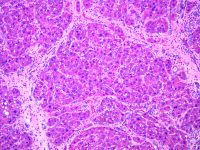

宫颈癌动物模型的构建

早期治疗宫颈癌的关键在于早期诊断。目前常用的方法较多,亦有一些新的诊断方法不断被介绍和采用,但各有优缺点,必须互相配合应用以提高早期诊断率。 一、阴道细胞学检查 多年临床实践证明,阴道细胞学检查是发现早期宫颈癌的一个很有价值的方法。由于癌细胞代谢快,凝聚力差,容易脱屑,取材及检查方法简便,准确率高,目前已普遍作为宫颈癌普查筛选的首要方法。 有关阴道细胞学检查的标本采取、检查方法及癌细胞的特征等。 国内杨大望报告阴道细胞学诊断正确

通常宫颈癌的发展较慢,如能早期发现、早期诊断、早期治疗、手术和放疗治疗的效果比较肯定,其预后较其他系统癌症为好。 公认影响宫颈癌预后的重要因素包括肿瘤分级、盆腔淋巴结转移、浸润深度和淋巴血管间隙的侵犯。一般来说,越是晚期患者预后越差,累积资料表明,Ⅰ期患者5年存活率为75%~90%,Ⅱ期为50%~70%,Ⅲ期为30%~35%,Ⅳ期为10%~15%。 经过数十年的研究,虽然我国在宫颈癌的防治方面取得了显著的成绩,但回顾过去,展望未来,还有许多工作